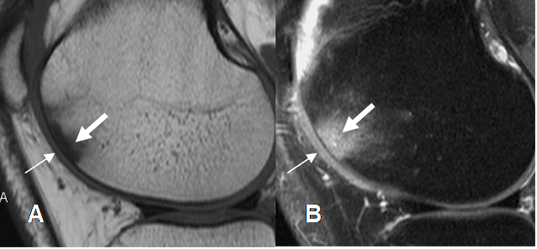

Fig 198. Artropatía degenerativa.

A: Rx AP y B: RM coronal en T1. Cambios degenerativos con formación de osteofitos (Flechas delgadas), disminución de los espacios femorotibiales, erosión de las superficies articulares y lesiones osteocondrales. (Flecha gruesa).